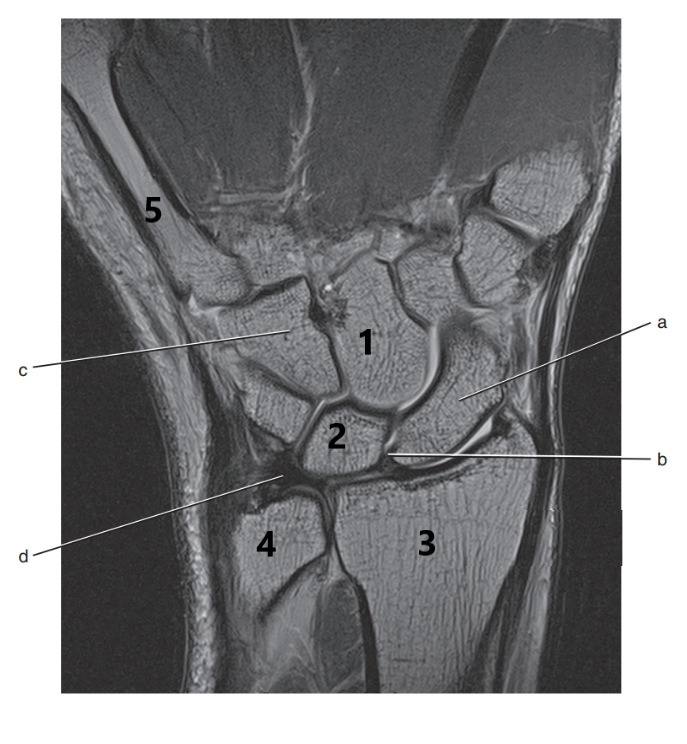

What is # 3 ?

Radius

What is letter a ?

Scaphoid

What is # 2 ?

Lunate

What is letter d ?

Triangular fibrocartilage complex

What is # 4 ?

Ulna